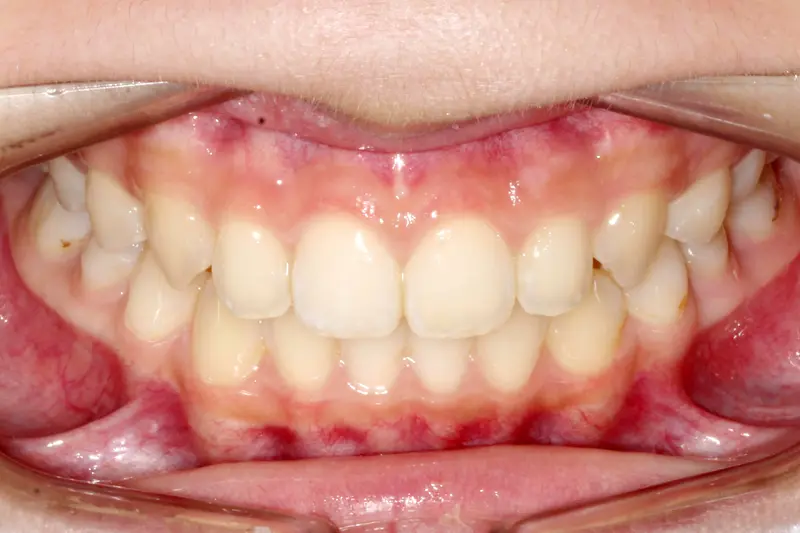

Crowding & Aesthetics 24 Months

The Non-Extraction Arc

The Diagnosis

Severe upper and lower crowding with a narrow maxilla. The smile appeared "hidden" due to the inward angle of the teeth.

The Engineering

We utilized a broad-arch wire sequence combined with passive self-ligating brackets to expand the smile width. By unraveling the crowding without removing teeth, we created a full, consonant smile arc that supports the facial soft tissue.

Instrument: Self-Ligating Brackets

After treatment: The Non-Extraction Arc

After

Before treatment: The Non-Extraction Arc

Before